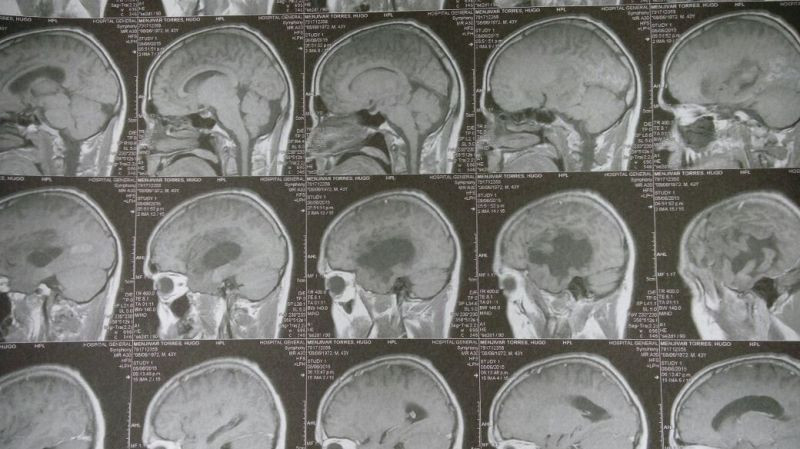

Oligodendroglioma temporal izquierdo Imagenes MRI Preoperatorio

Oligodendroglioma temporal Imagenes MRI Preoperatorio